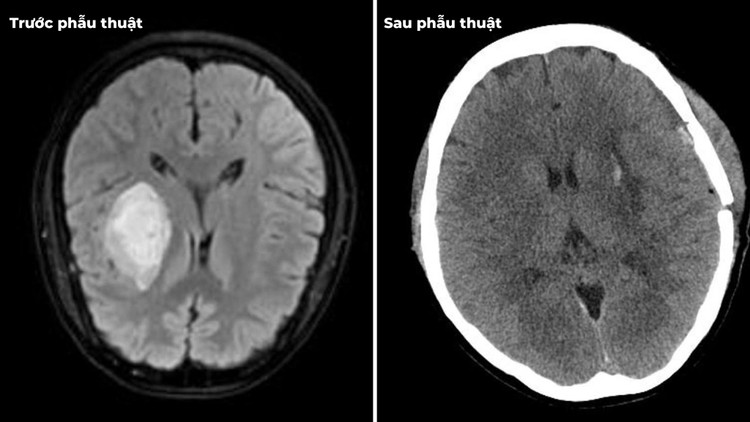

| Xuất huyết não do tăng huyết áp trên phim chụp trước và sau mổ - Ảnh BVCC |

Theo ước tính, khoảng 80% bệnh nhân bị xuất huyết não có tiền sử tăng huyết áp. Xuất huyết não xảy ra khi máu thoát ra khỏi mạch và tràn vào nhu mô não, có thể xuất hiện ở nhiều vị trí trong não như bên trong não, giữa não và màng bao phủ, hoặc giữa hộp sọ và vỏ não.

Khi máu tổn thương và tập trung thành khối tụ máu, mô não sẽ bị phù nề, gây áp lực lên các mô xung quanh, dẫn đến tổn thương tế bào não và vỡ mạch máu. Tình trạng này có nguy cơ tử vong rất cao, đặc biệt nếu khối máu tụ lớn